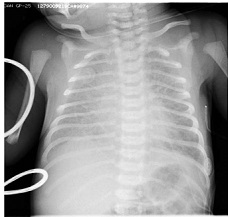

Неонатальное ОГК

The diaphragms lying at the level of the 8th ribs posteriorly and 6th ribs anteriorly.

Диафрагма расположена между задними отрезками 8-х ребер и передними отрезками 6-х.

The transverse cardiothoracic ratio should be <60%.

Поперечный кардио-торакальный индекс должен быть меньше 60%.

Источник: R. Arthur. The neonatal chest X-ray